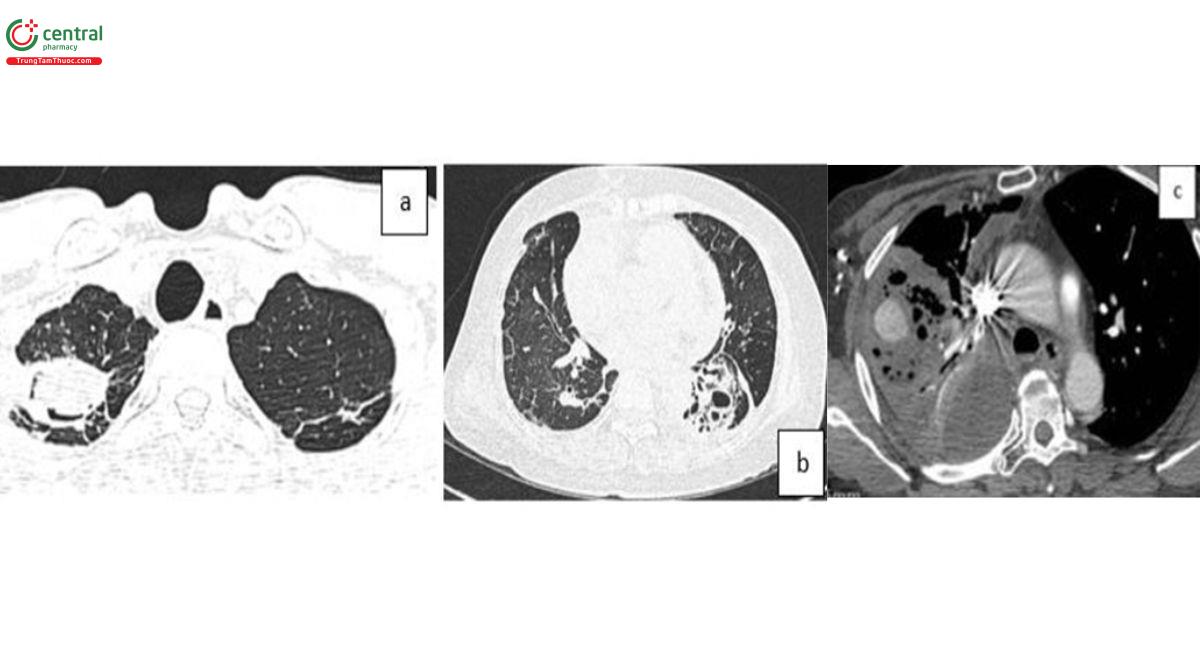

5.2 Đánh giá vị trí xuất huyết nhu mô phổi và đường dẫn khí

CLVT có thể xác định chính xác vị trí chảy máu trên 63-100% trường hợp ho ra máu. Hậu quả chảy máu lấp đầy các phế nang và đường dẫn khí gây ra hình ảnh “đông đặc” hoặc “tổn thương dạng kính mờ”. Cục máu đông cũng có thể hình thành làm bít tắc nhánh phế quản gây xẹp phổi [8]. Những dấu hiệu trên không đặc hiệu, gặp trong nhiều nguyên nhân khác nhau, nhưng có thể giúp dự đoán vị trí chảy máu. Trường hợp có nhiều vị trí có tổn thương dạng kính mờ, vị trí chảy máu được xác định là ở phần thùy phổi có kích thước lớn và đậm độ cao nhất [9].

![Hình 1. Các tổn thương kính mờ trên bệnh nhân ho ra máu (các mũi tên). Phần tổn thương kính mờ tại thùy dưới phổi (T) là ưu thế nhất, xác định vị trí xuất huyết [9].](/images/item/ho-ra-mau-1.jpg)